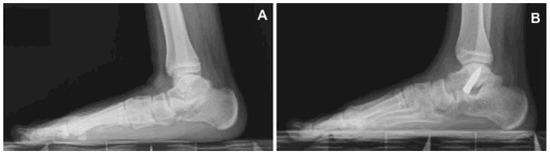

All patients with symptomatic flexible flatfoot, defined by clinical and radiographic evaluation, and resistant to nonoperative treatment, underwent the anterograde calcaneo-stop procedure [3] performed under local anesthesia, without tourniquet, with or without sedation. The patient was placed supine, the operated extremity was rotated slightly inwards with a 90° bended knee and the supinated foot was kept by the assistant leaning on the fluoroscopic machine to allow clear fluoroscopic control. An incision of 1 cm was applied centered on the sinus tarsi. An entry hole was made into the talus with a trocar and a steel screw (VCA, Mikai®, Genoa, Italy) of the desired diameter and length (6.5 mm × 35 mm, 8 mm × 35 mm, or 8 mm × 40 mm) was percutaneously inserted at a 35° direction in the sagittal and 45° in the coronal plane (Figure 1). The dorsiflexion of the foot was checked with the knee in extended position. No cast immobilization was required. Patients were allowed for full weight bearing the same day of the surgery or as soon as possible. Foot exercises and active and passive ankle joint mobilization were recommended post-operatively. The screw was scheduled for removal 24–26 months after the first surgical procedure.

Figure 1. Symptomatic flexible flatfoot (A) treated with an anterograde calcaneo-stop procedure (B).